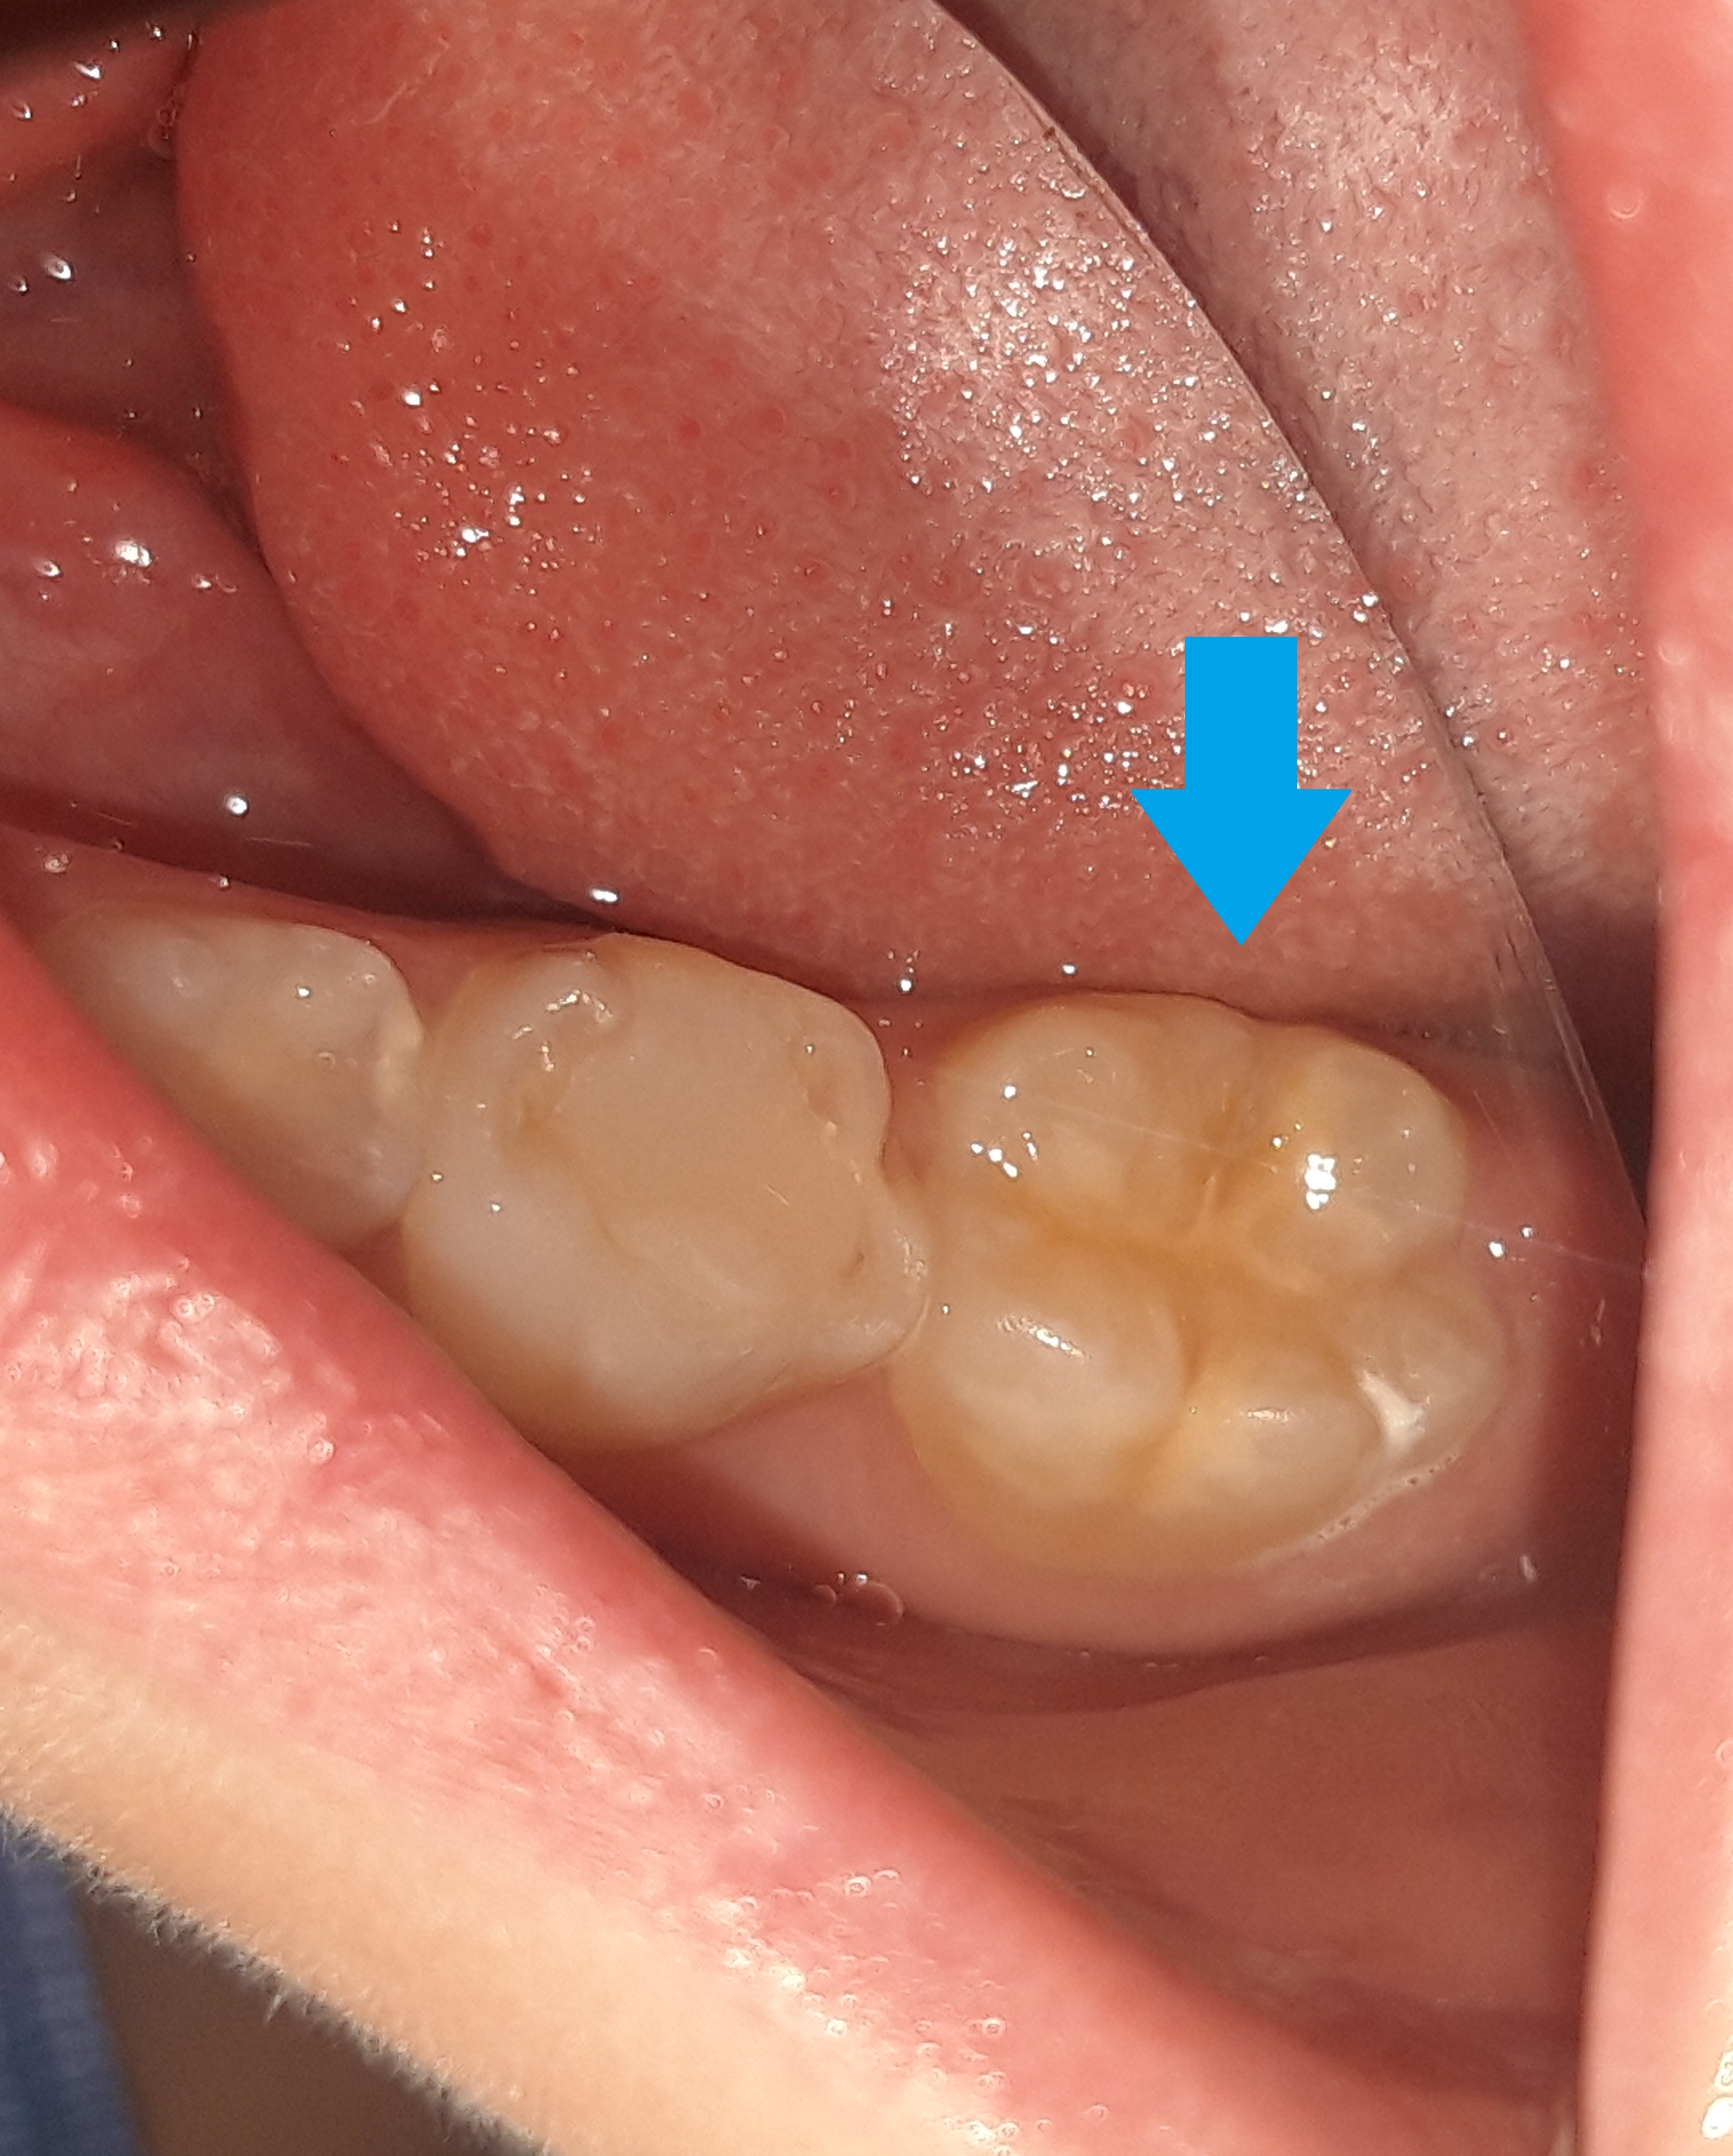

Στα πλαίσια του ετήσιου προληπτικού οδοντιατρικού ελέγχου πραγματοποιήθηκε στο μικρό ασθενή προληπτική κάλυψη οπών και σχισμών (sealant) στον πρώτο αριστερό μόνιμο γομφίο της κάτω γνάθου.

ΠΡΙΝ

ΜΕΤΑ